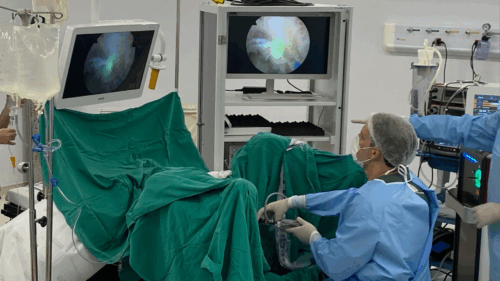

“O HoLEP é uma cirurgia minimamente invasiva feita por via uretral, sem cortes externos. Usamos um laser de Hólmio para separar e remover o tecido interno da próstata que está causando a obstrução, como se descascássemos a parte interna de uma fruta”, explica o Dr. Leonardo. Esse tecido é empurrado para a bexiga e removido por um equipamento chamado morcelador, que o fragmenta e aspira.

O laser de Hólmio é o principal diferencial do HoLEP. Ele permite cortes precisos com excelente coagulação, reduzindo sangramentos e tempo cirúrgico. O procedimento conta ainda com equipamentos como o ressectoscópio, que permite visualização interna, e o morcelador, responsável por aspirar o tecido removido.

Contudo, o Dr. Leonardo alerta: “O HoLEP exige treinamento especializado e experiência. Nem todo urologista está habilitado para essa técnica. Na UROBH, investimos constantemente na formação da equipe e na atualização tecnológica para garantir o melhor resultado aos pacientes.”